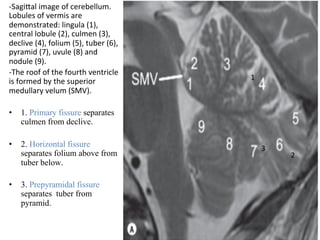

-SagiTal	image	of	cerebellum.

Lobules	of	vermis	are

demonstrated:	lingula	(1),

central	lobule	(2),	culmen	(3),

declive	(4),	folium	(5),	tuber	(6),

pyramid	(7),	uvule	(8)	and

nodule	(9).

-The	roof	of	the	fourth	ventricle

is	formed	by	the	superior

medullary	velum	(SMV).

•  1. Primary fissure separates

culmen from declive.

•  2. Horizontal fissure

separates folium above from

tuber below.

•  3. Prepyramidal fissure

separates tuber from

pyramid.